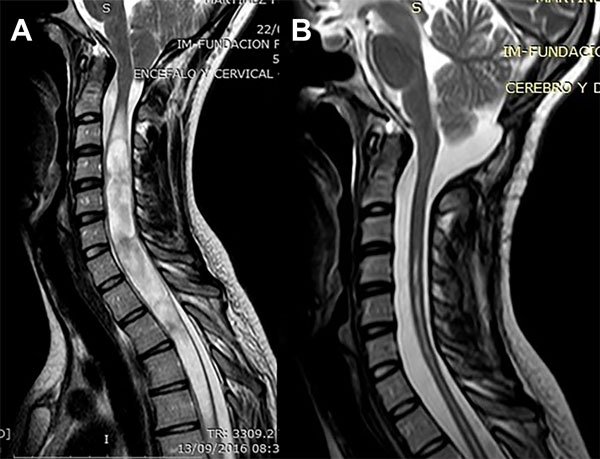

Caso 2: Oligosintomático

Una paciente de 23 años de edad consultó por parestesias y adormecimiento en ambas manos de 9 meses de evolución sin una progresión clara. El examen neurológico sólo mostró una disminución de la sensibilidad táctil y dolorosa en los extremos de los dedos de ambas manos. La RM mostró un descenso amigdalino de 17,8 mm y una SM entre C3 y T12 con ocupación completa del canal cervical (Figura 4A). La RM en contraste de fase mostró a nivel de la unión occípito-cervical una velocidad de circulación del LCR de 6,6 cm/segundo. Fue llevada a cirugía y se le realizó una descompresión cráneo espinal y duraplastia con periostio. Luego de una evolución postoperatoria satisfactoria fue dada de alta a las 96 horas. A los 3 meses los síntomas previos remitieron. En la RM de control la SM había desaparecido (sólo persistía una cavidad residual) (Figura 4B) y la velocidad de circulación del LCR se había normalizado a 3 cm/seg. En su último control, 6 años después, la mejoría clínica e imagenológica era total.

Figura 4: Caso 2. A: RM de columna cervical en plano sagital ponderada en T2 que muestra una siringomielia cervicodorsal extensa con ocupación completa del canal. B: RM de columna cervical en plano sagital ponderada en T2 postoperatoria que muestra la resolución de la siringomielia.

Caso 5: Control evolutivo postoperatorio

Un varón de 22 años de edad, deportista de contacto profesional, consultó por presentar una MCI con SM. Sólo presentaba apneas de sueño confirmadas por una polisomnografía. La RM mostraba un descenso amigdalino de 17 mm y una SM ubicada entre C3 y C4 (Figura 7A-B). Teniendo en cuenta su profesión y los síntomas se indicó cirugía. Se le realizó una descompresión cráneo cervical y duraplastia con periostio. La evolución postoperatoria transcurrió sin complicaciones. A los 5 meses de la cirugía se le realizó una RM en contraste de fase en donde se observó que la SM no se había reducido y las velocidades del LCR eran de 10 cm/seg. Siguió bajo control y a los 16 meses de la cirugía se observó la desaparición de la SM (Figura 7C) y en la nueva RM en contraste de fase la normalización de las velocidades del LCR (2,3 cm/seg.). Fue dado de alta definitivamente pudiendo reasumir su actividad deportiva.

Figura 7: Caso 5. A: RM de cerebro en plano sagital ponderada en T2 que muestra el descenso amigdalino de 17 mm de configuración de bordes agudos y el extremo proximal de una siringomielia cervical. B: RM de columna cervical en plano sagital ponderada en T2 que muestra una siringomielia entre C3 y C4. C: RM de columna cervical en plano sagital ponderada en T2 que muestra la resolución de la siringomielia.